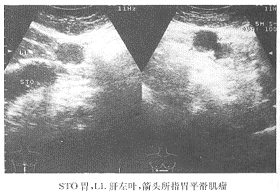

2.腹部B超檢查 採用飲水法超聲檢查可清晰顯示腫瘤的部位大小、生長方式及其內部回聲結構,對診斷胃平滑肌瘤有一定價值,缺點是難以確定其性質和組織來源若能結合胃鏡活檢檢查,則可大大提高診斷率聲像顯示平滑肌瘤邊緣光滑內呈均勻性低回聲。